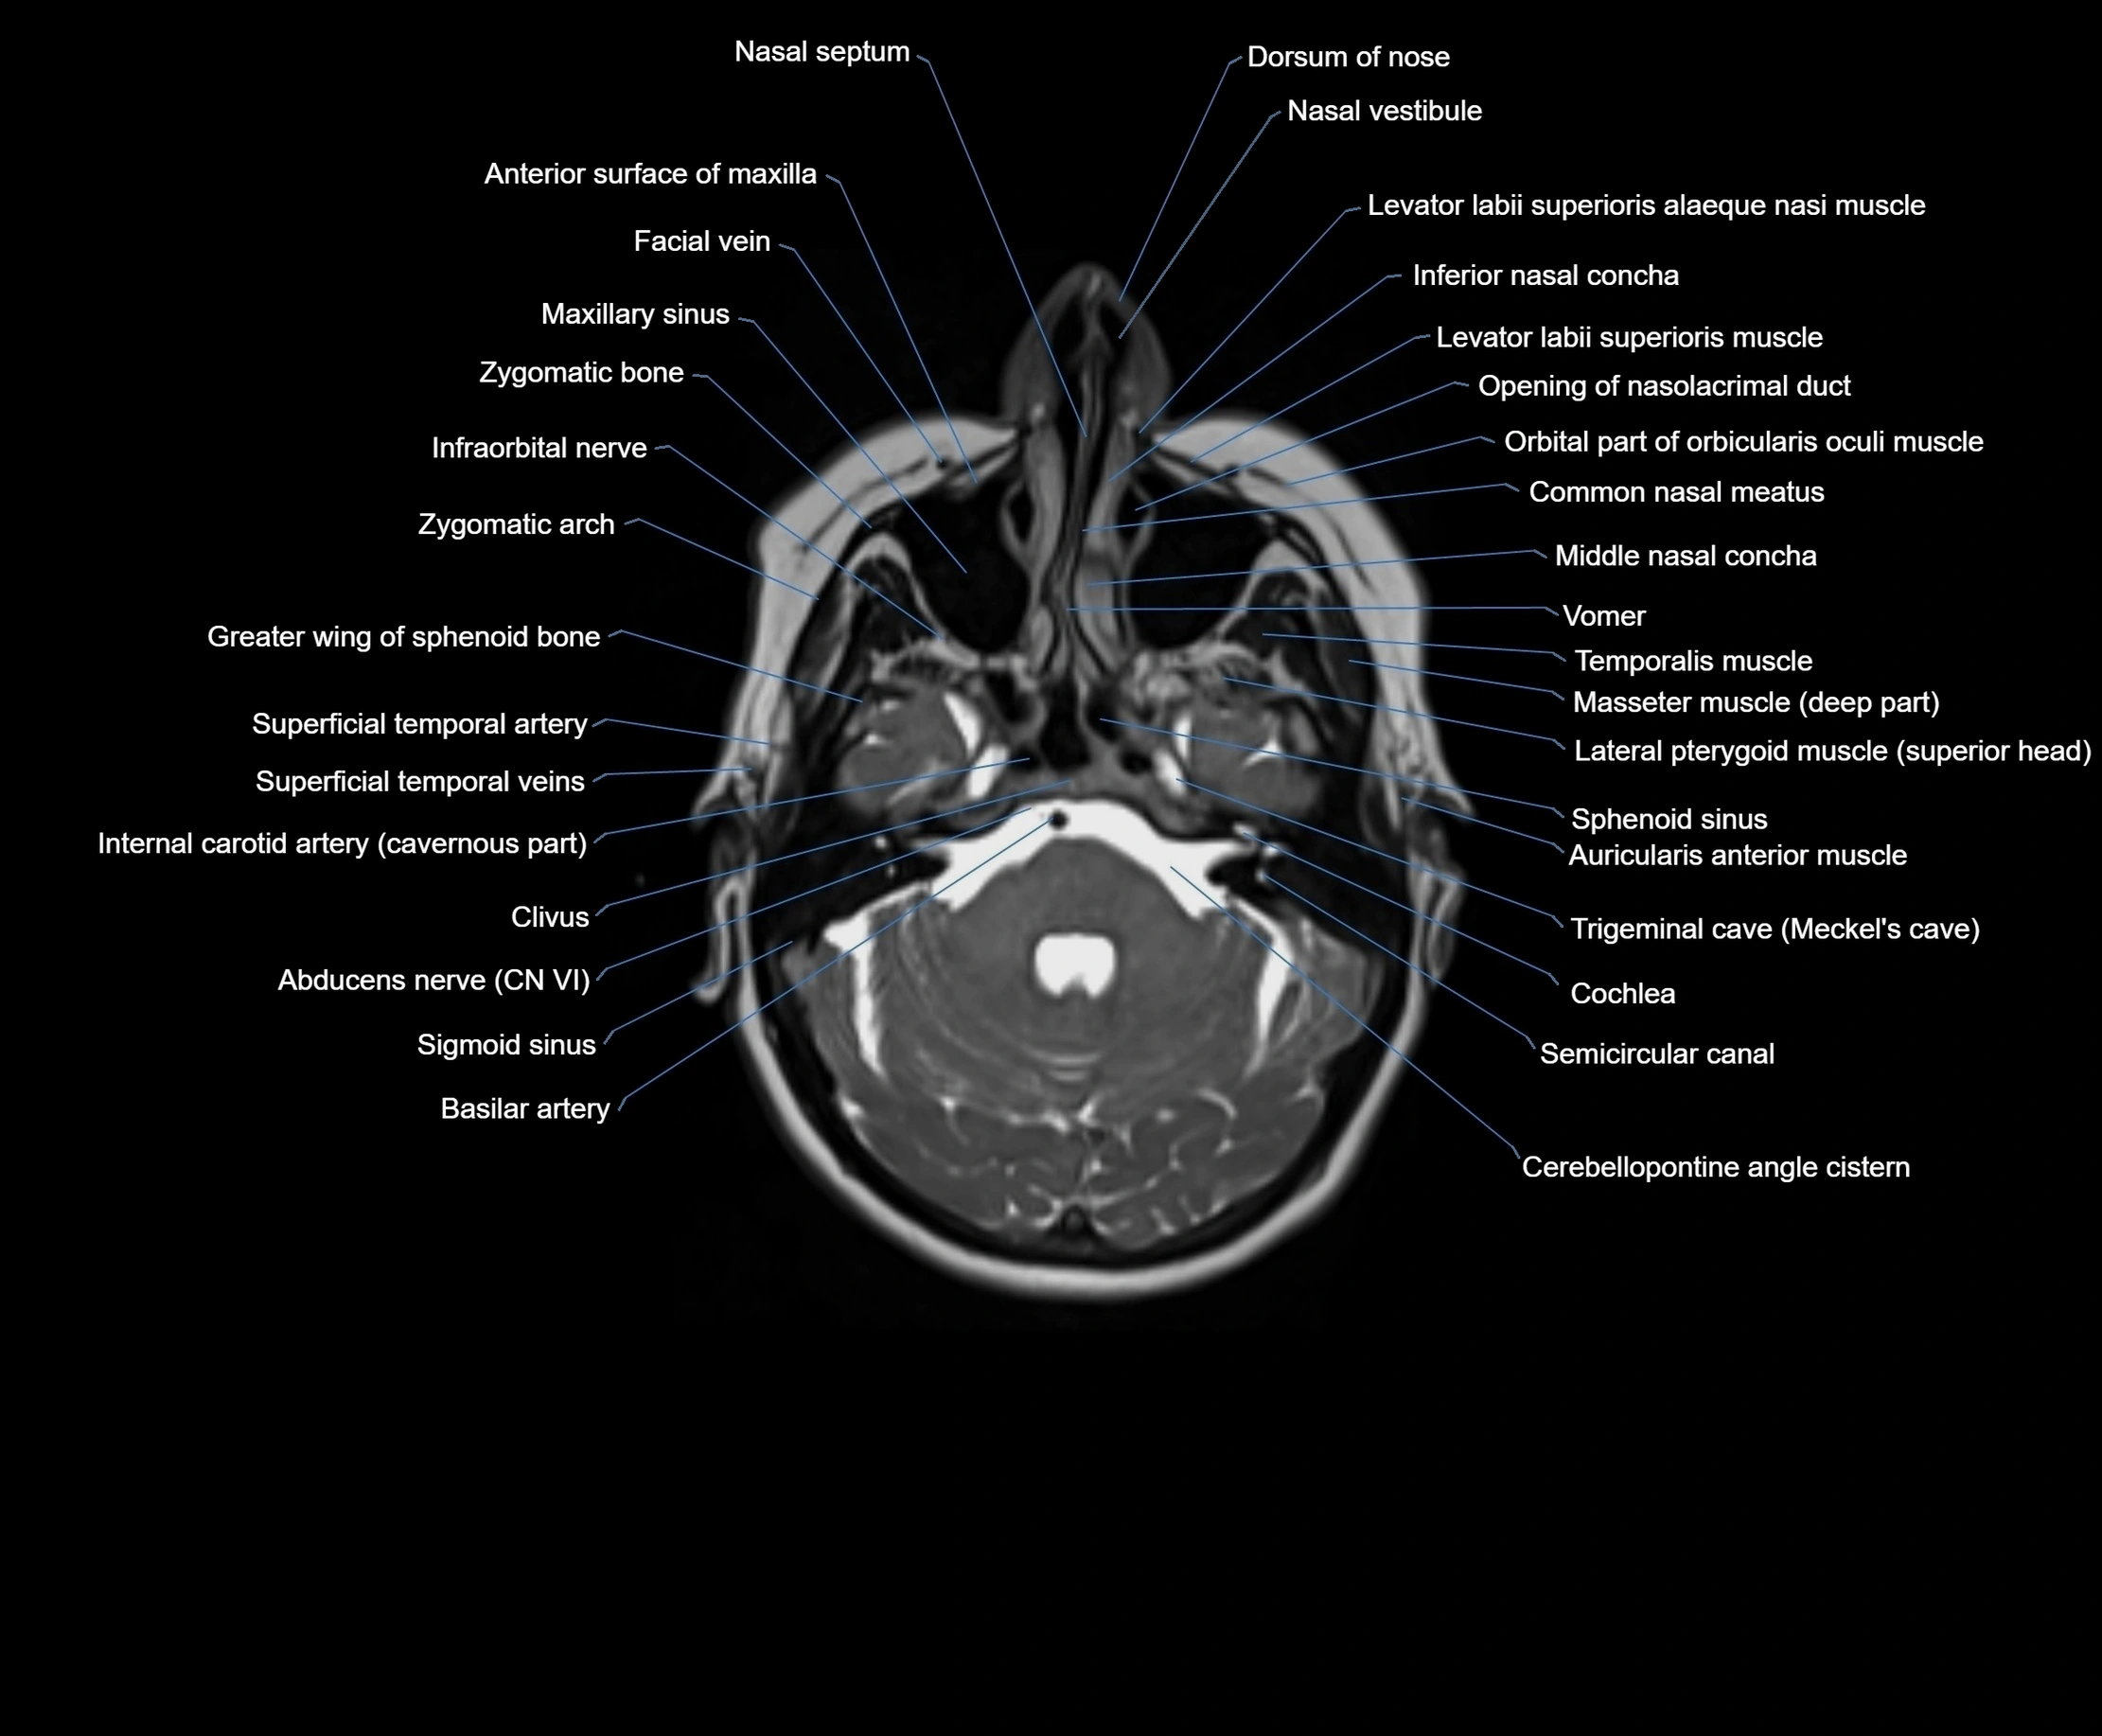

MRI images